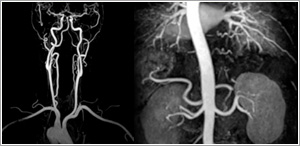

MR Angiography (MRA)

This technique uses flowing blood to obtain detailed images of the blood vessels. The examination is fast and easy to do, and produces images that approach the quality of traditional invasive catheter angiography.